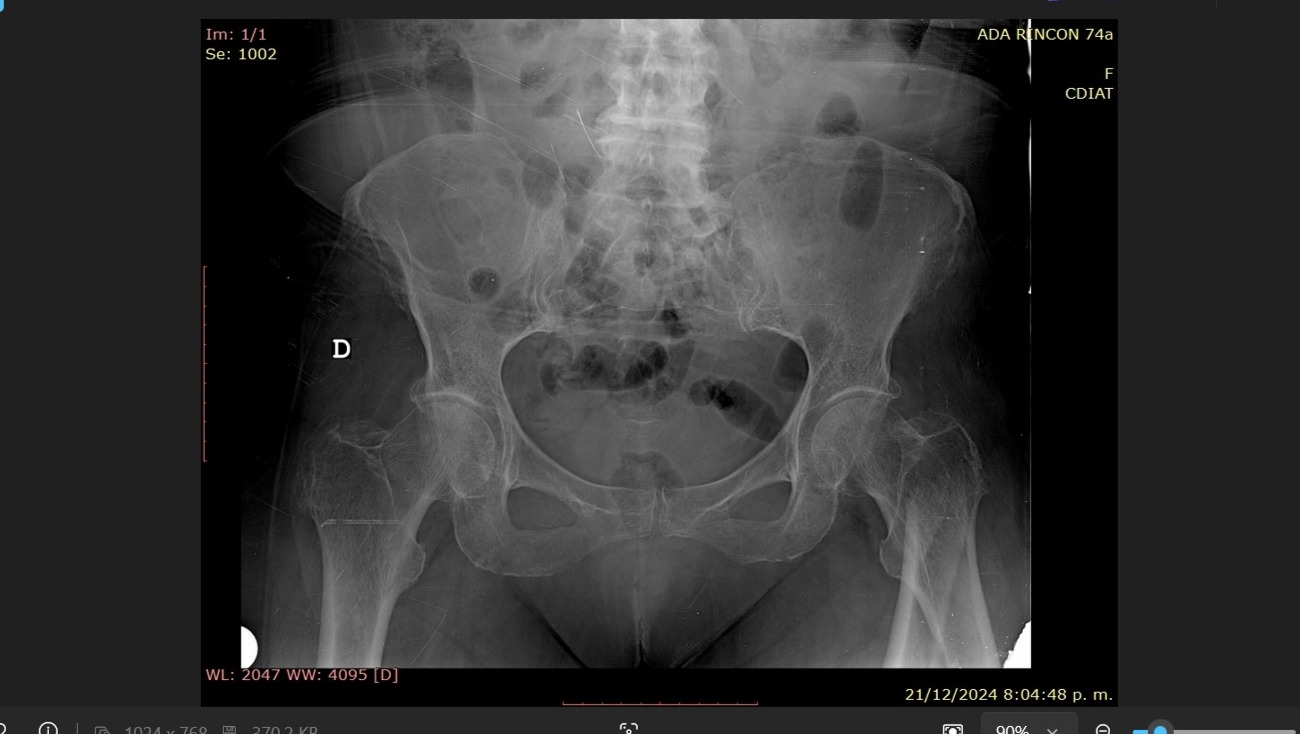

Ese día, mientras cocinaba con el mismo amor con el que siempre ha cuidado de nuestra familia, el hueso de su pierna (fémur) se fracturó de manera inesperada. No fue una caída, sino el impacto silencioso de años enfrentando osteoporosis y sarcopenia, condiciones que han ido debilitando su cuerpo pero nunca su espíritu.

La operación está programada en el Centro Clínico Valentina Canabal CA e incluye la colocación de un Sistema de Clavo Bloqueado para Fracturas Inter y Sub Trocantéricas.